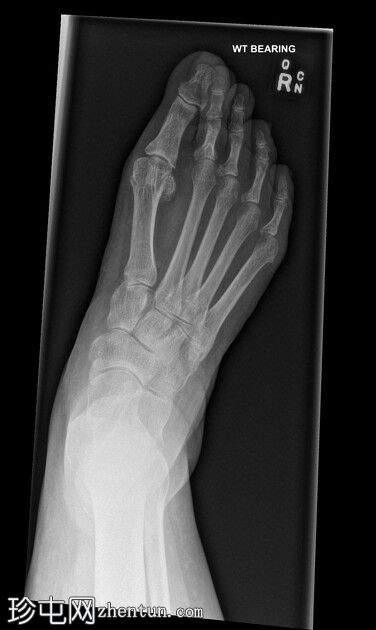

正位片

第二趾交叉畸形,跖趾关节伸展,足趾内旋,压在相邻拇趾背侧。

第二趾内旋,压在拇趾上。患者有长期穿高跟鞋的病史。